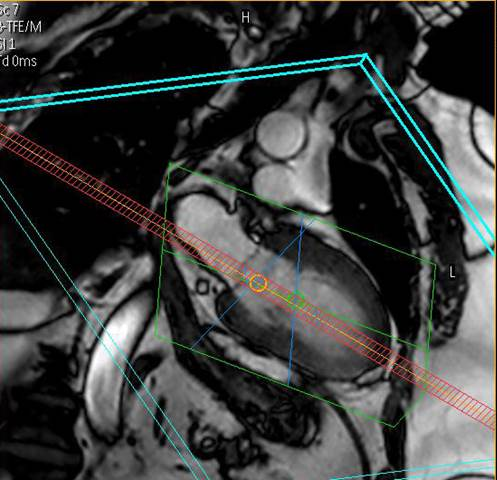

spielt seit der Erstinstallation eines MR-Tomographen im Jahr 1996 eine weltweit führende Rolle bei der klinischen Anwendung, Forschung und Ausbildung auf dem Gebiet der CMR. Wir untersuchen mit zwei MRT-Systemen

modernster Bauart pro Jahr ca. 3000 Patienten, wobei das gesamte diagnostische Spektrum abgedeckt wird.

Wir bieten modernste MRT-Diagnostik.

Ganzkörper MR System - Philips healthcare